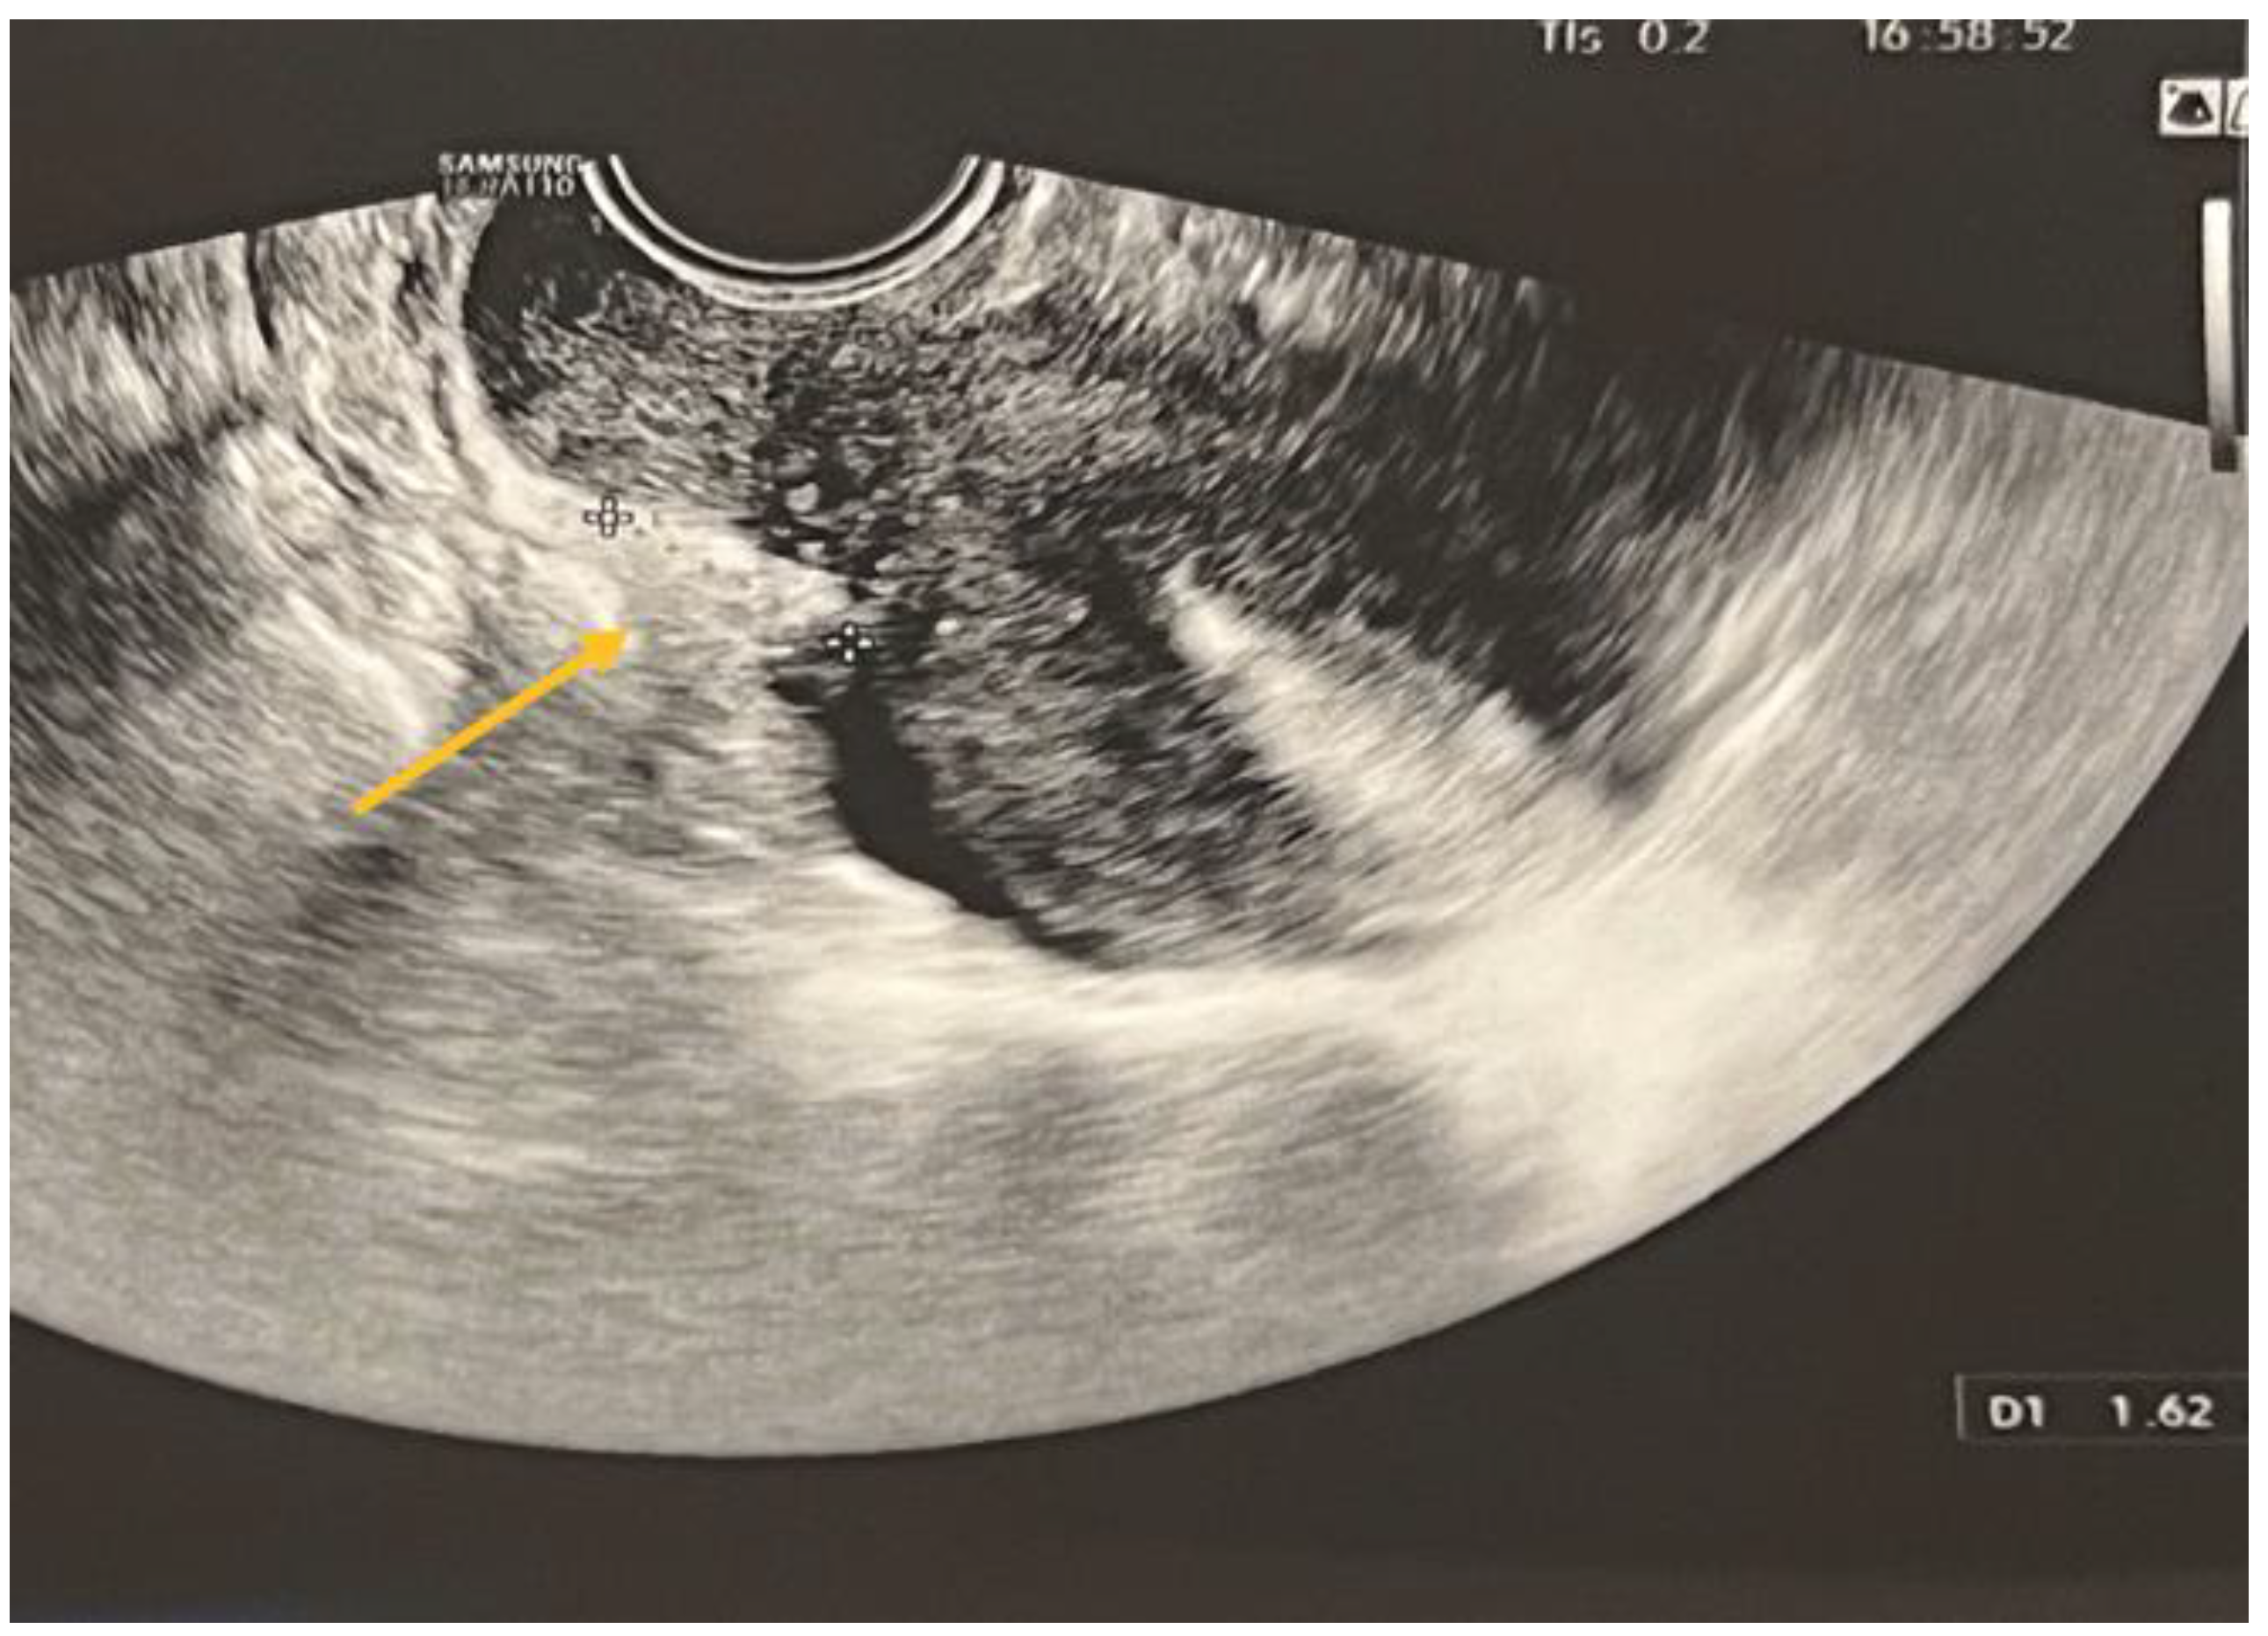

TVS is a reliable diagnostic tool for ovarian endometriomas (OMA), which can be readily identified due to their characteristic ground-glass appearance, which lacks any discernible vascular echo when assessed with a Doppler flow scanner, as depicted in Figure 3 [9,10].

The statistical analyses, namely the Chi-square χ2 test (df = 1) = 80.85, p < 0.001, and Fisher’s exact test p < 0.001, indicate a statistically significant connection. Therefore, within this cohort, the ultrasound diagnostic aligns with the intraoperative diagnosis for endometriomas. The specificity of the diagnostic test is 57.14%, indicating that it correctly identifies individuals without the condition. The sensitivity is 93.78%, indicating that it accurately detects individuals with the condition. The diagnostic accuracy, which is a significant measure, is 84.47%. The value of Cohen’s kappa coefficient was found to be 0.55, which indicates a moderate level of agreement. The statistical significance of this result was confirmed with a p-value < 0.001.

Figure 3. TVS aspect of endometrioma.